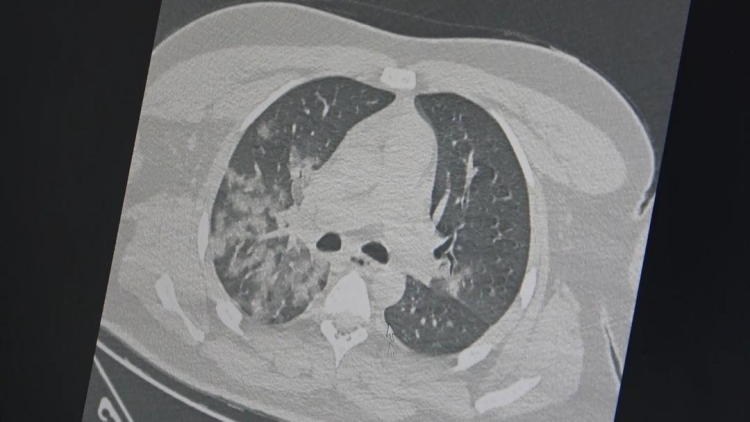

Göğüs Hastalıkları Uzmanı Prof. Dr. Şevket Özkaya, son dönemde artan ani genç ölümlerinin ardında Kovid-19'un damar yapısına verdiği hasarın etkili olduğunu açıkladı. Prof. Dr. Özkaya, özellikle gençlerin, Kovid-19 sonrasında bozulmuş damar yapılarının ağır egzersiz ve sporla birleştiğinde ölümcül kalp krizlerine neden olabileceğini vurguladı. Detaylar haberimizde…

Son dönemde acil servislerde gençlerde görülen ani ölümlerinçoğunun akciğer ve kalp-damar hastalıklarından kaynaklandığına dikkat çeken Özkaya, Kovid-19'un damar yapısına verdiği zararın bu ölümlere yol açtığını, aşıların ise herhangi bir rolü olmadığını belirtti. Prof. Dr. Şevket Özkaya, açıklamalarda bulundu.